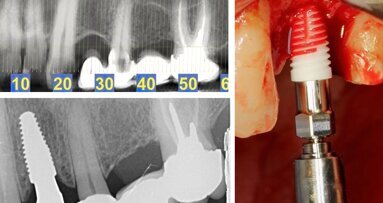

El Dr. Olivier Chéron, Especialista en Implantología y en implantes cerámicos, ejerce en Barcelona, donde es co-director del Club ITI Barcelona, co-fundador de la Clínica Dental Equilibria y Miembro de AFNOR.